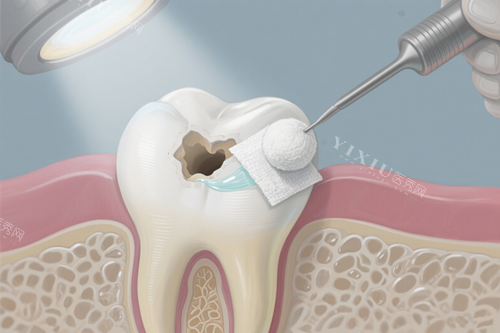

三、台州补牙 / 修复价格表:树脂 200 元起,全瓷牙 / 烤瓷牙 / 嵌体按需选

补牙和修复是高频需求项目,台州牙科医院根据材料和功能差异,提供多档选择:

普通树脂补牙(国产):200 元起 / 颗(基础龋齿修复,适合后牙)

美国 3M 纳米树脂补牙:350 元起 / 颗(色泽逼真,前牙美学修复优选)

义获嘉树脂补牙:500 元起 / 颗(高耐磨性,适合磨牙长期使用)

嵌体补牙(瓷嵌体):1300 元起 / 颗(密合度高,替代大面积补牙)

钴铬合金烤瓷牙:600 元起 / 颗(经济实惠,适合后牙过渡修复)

国产爱尔创全瓷牙:1200 元起 / 颗(无金属,前牙美观修复)

德国威兰德全瓷牙:2500 元起 / 颗(硬度高,后牙高强度修复)

铸瓷贴面(超薄款):3000 元起 / 颗(小创口美白,改善氟斑牙 / 四环素牙)